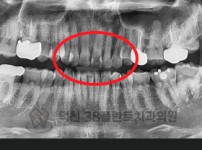

치료전후